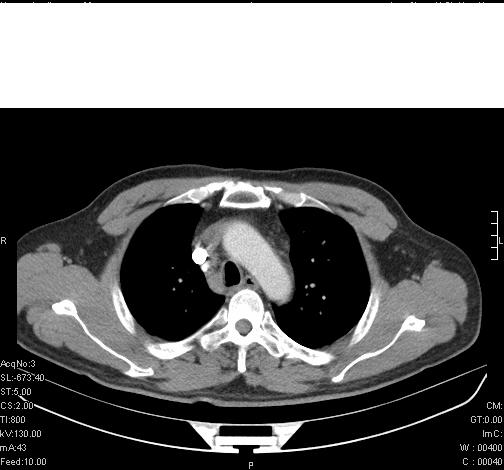

标题: CT6685:右肺阻塞性炎症,增强CT。

前几天,发了患者的平扫片,患者抗炎一周后增强扫描。右中叶病灶吸收明显,但下叶病灶未见明显吸收。右肺门可见结节影,看来凶多吉少

第18幅,好像不能简单用炎症解释,前几天我发平扫时,90%人支持肺癌,现在好像大家更倾向于炎症了,我觉得还是不能排除肺癌。

还是考虑右肺中央型肺癌可能性大

考虑右肺中央型肺癌可能性大

右主支气管狭窄,管壁增厚。考虑右中心性肺ca伴阻塞性肺炎。

既然抗炎治疗有效,可继续治疗;右肺下叶支气管管腔狭窄,管壁增厚,右下肺见斑片状高密度影,右侧主支气管后见结节影(淋巴结?),肺癌不能排出。